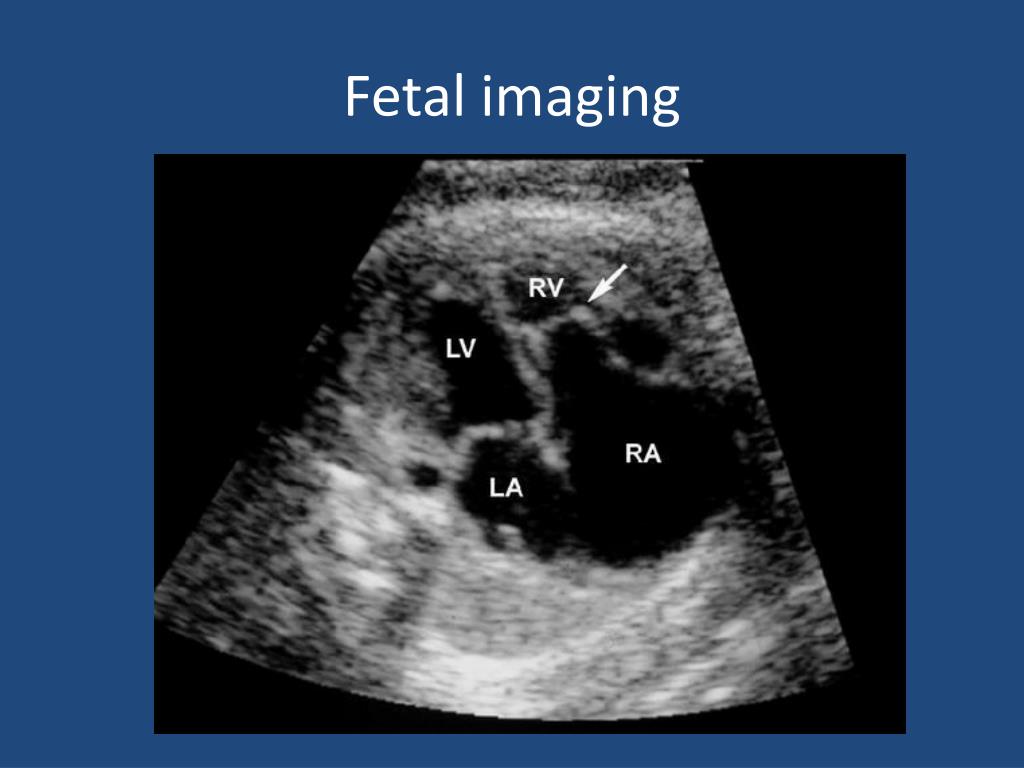

8. Fetal imaging